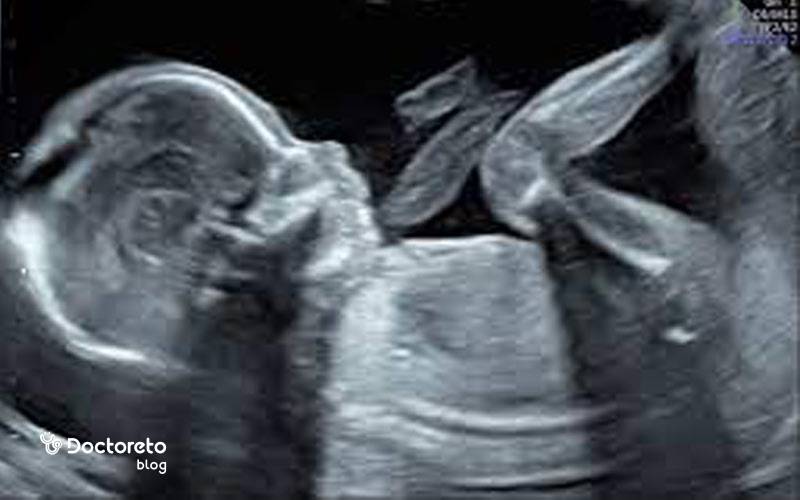

عکس جنین ۱۸ هفته دختر و پسر

عکس جنین ۱۸ هفته دختر و پسر را مشاهده می‌کنید.

عکس جنین ۱۸ هفته در سونوگرافی

عکس جنین ۱۸ هفته در سونوگرافی را مشاهده می‌کنید.